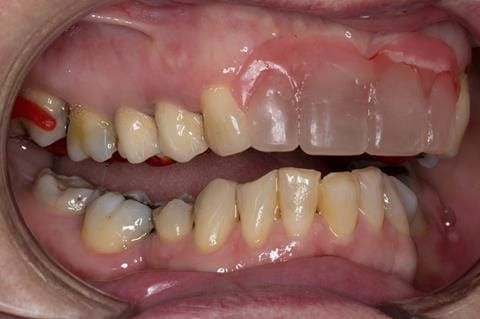

- UR2 peri-radicular periodontitis with a peri-radicular area on the root apex. Retrograde amalgam filling from a previous apicectomy. No visible root canal or root canal filling. Large circumferential marginal gap between the crown and tooth. Large post and core present. Very little tooth structure remaining resulting in a fragile tooth with increased potential for fracture.

- UR1 peri-radicular periodontitis with a small peri-radicular area on the root apex with wide blunderbuss apex. Radio-opaque root canal filling present approximately 3 mm short of the radiographic apex. Large circumferential marginal gap between the crown and tooth. Large post and core present. Very little tooth structure remaining resulting in a fragile tooth with increased potential for fracture.

- UL1 peri-radicular periodontitis with a peri-radicular area on the root apex. Retrograde amalgam filling from a previous apicectomy. Visible root canal space with no sign of root canal filling. Large circumferential marginal gap between the crown and tooth. Large post and core present. Very little tooth structure remaining resulting in a fragile tooth with increased potential for fracture.

- UL2 peri-radicular periodontitis with a peri-radicular area on the root apex. No visible root canal or root canal filling. Large circumferential marginal gap between the crown and tooth. Large post and core present. Very little tooth structure remaining resulting in a fragile tooth with increased potential for fracture.

- High smile line showing gum above gingival zeniths of upper front teeth when smiling. Aesthetic failure of the upper four incisors with inflammation of the gingivae and mis-match of the gingival zenith levels.